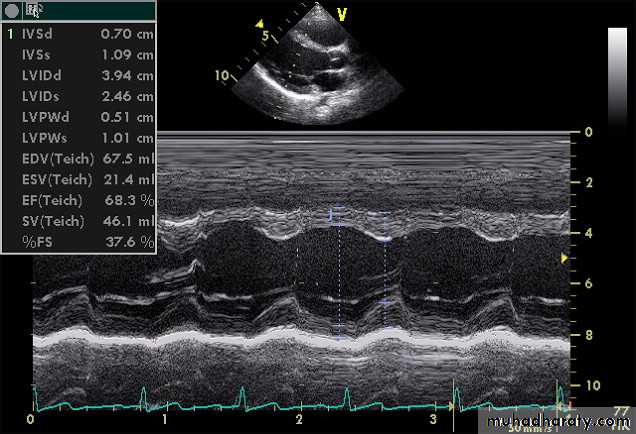

3-ECHOCARDIOGRAPHY

Echo studies may confirm enlargement of ventricular chambers and impaired LV systolic function(low fractional shortening or ejection fraction) as well as impaired diastolic function by the use of Doppler techniques.